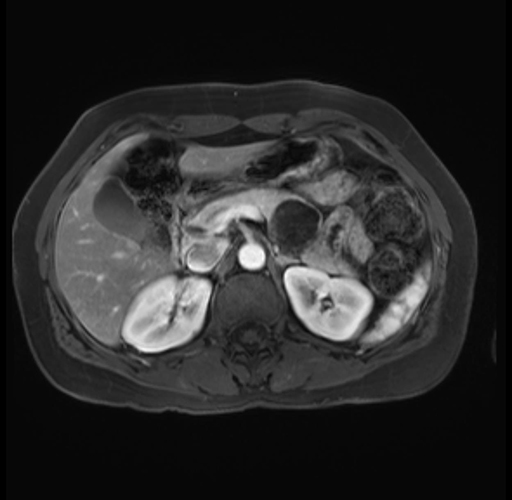

Imaging Analysis

Look through the patient's CT scan to identify any areas of concern for the necessary procedure.

Based on your CT findings, which issue(s) are present and would give reason for "planned slowing down moment(s)" in this case?

Considering a standard distal pancreatectomy procedure, what step(s) of the operation would you do differently in this case?